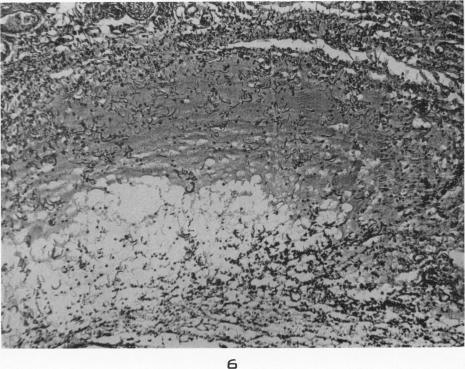

Lack of cortisone effect in the early stages of inflammation and repair.

Am J Pathol. 1953 Jan-Feb;29(1):1-19.